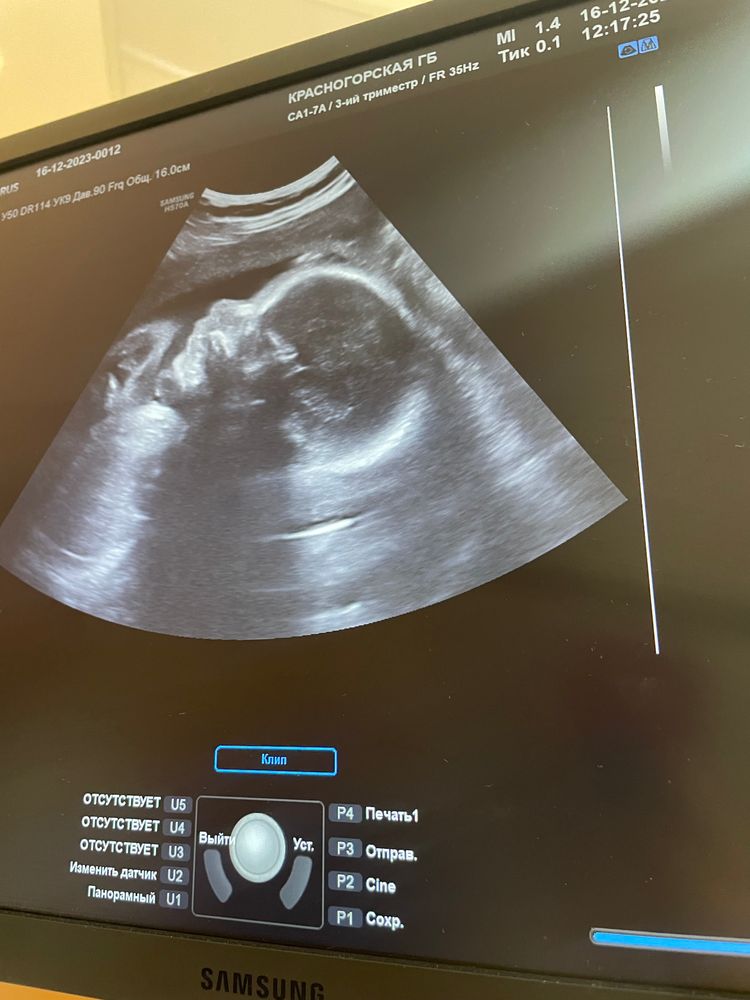

36 недель 🐳👼🏼🩷

Сегодня еду заключать контракт на роды .. мы почти прошли эту игру 👀..🙈 три дня назад была на узи , все соответствует срокам, только ноги почти на 37 недель, но д

Зоя Сергеевна растет , уже ее пинки отчетливо видно, чувствую как икает .🩷🩷🩷🩷🩷 вышла в официальный декрет , но продолжаю работать 🙈 посетила мониаг , 😒 начал